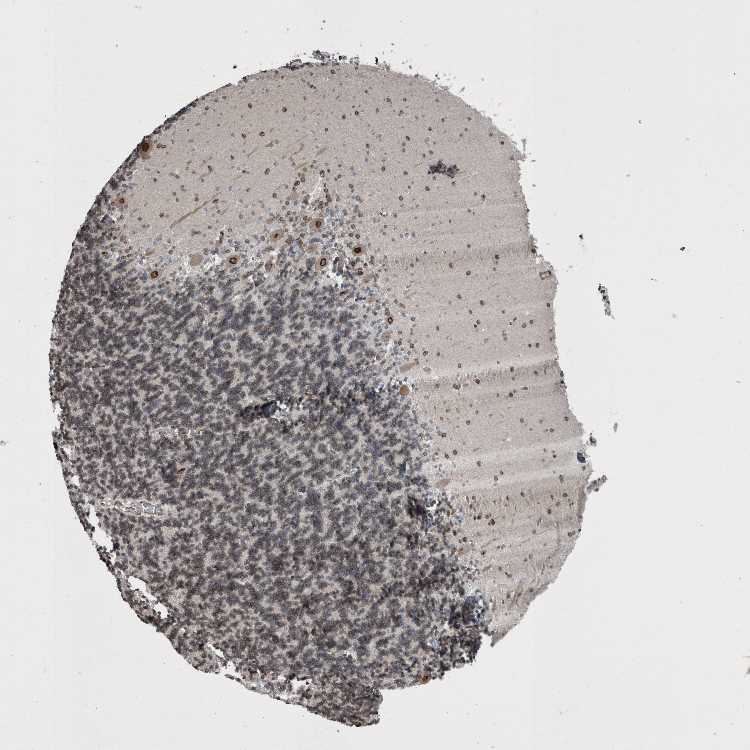

CEREBELLUM - Antibody stainingi

Antibody staining in the annotated cell types in the current human tissue is reported as not detected, low, medium, or high, based on conventional immunohistochemistry profiling in selected tissues. This score is based on the combination of the staining intensity and fraction of stained cells.

Each image is clickable and will lead to virtual microscopy that enables deeper exploration of all samples and also displays staining intensity scores, fraction scores and subcellular localization as well as patient and tissue information for each sample.

Antibody HPA018437Antibody HPA023960Antibody HPA049497Antibody HPA051675Antibody CAB034063

Purkinje cells MediumHighLowNot detectedNot detected

Cells in granular layer Not detectedMediumMediumLowMedium

Cells in molecular layer LowMediumLowNot detectedHigh